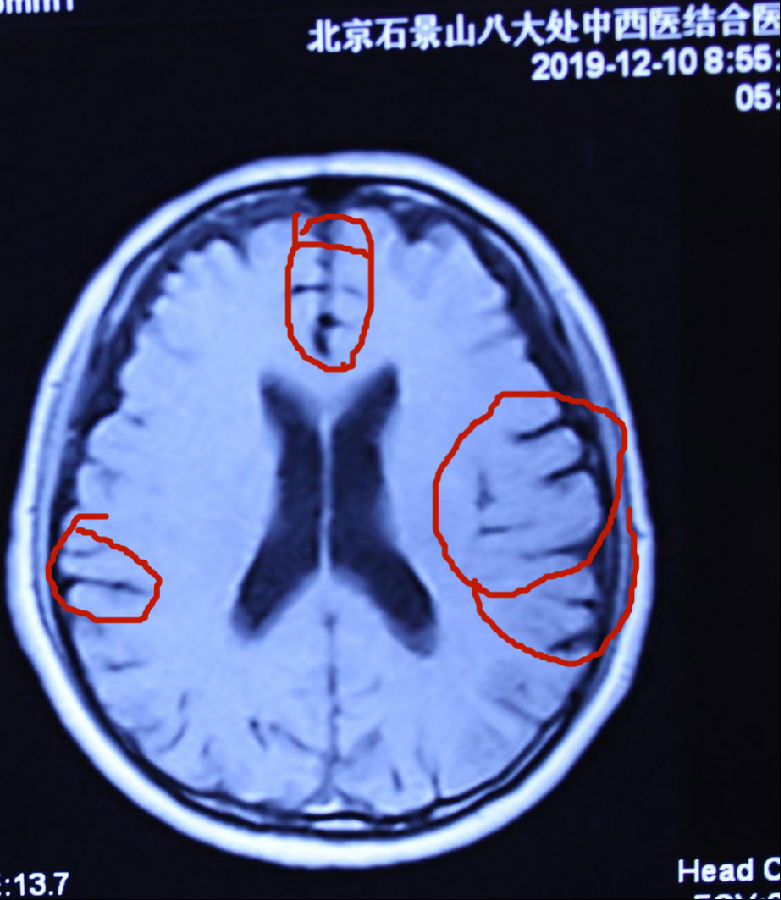

张先生核磁共振片其中单图的治疗前后比较:

2019年4月16日前见片治疗脑萎缩严重。病情严重。 2019年7月9日治疗后见片脑萎缩减轻。病情治愈。

脑组织逆生长的情况见左右两个图内红圈相对等部位的比较,圈内白色的部分是脑组织,圈内黑色的部分是没有脑组织了是萎缩后空缺的现象,黑色越多脑萎缩越严重,白色越多脑组织越多,脑组织多了,就是改变了脑萎缩,就是脑组织逆生长,因此,通过中药使脑组织逆生长就消除了和治愈了脑部的疑难病。该患者的阿尔茨海默症通过纯中药达到了脑组织逆生长,患者的记忆障碍就正常了,病情就治愈了。 实践证明阿尔阿尔茨海默症的发病,不仅是现代医学认为的海马体萎缩的问题,是脑部整体出现了问题,也不是不可治愈的疾病,是能够治愈的。我们经过几十年的研究探讨创新,用纯中药治愈阿尔茨海默症是科学的真实有效的!只要是脑组织逆生长,阿尔茨海默症就必然能够治愈。 |